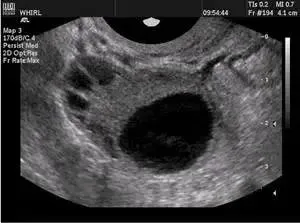

健康科普 | 好“孕”第一步——卵泡的超声监测